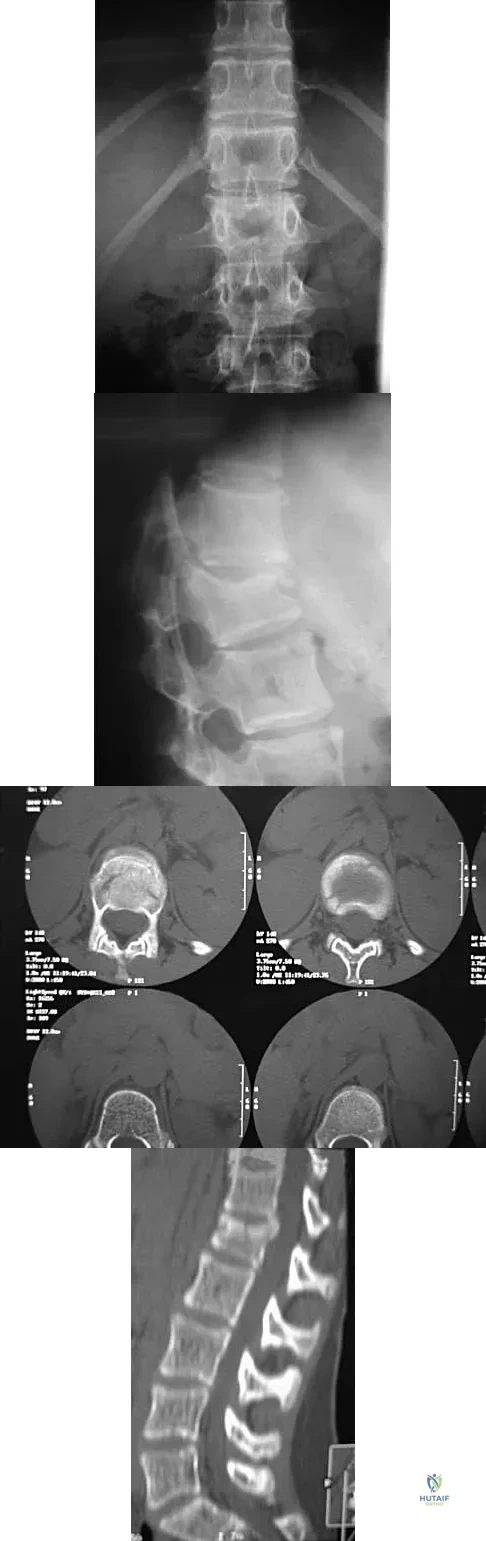

A skeletally mature 15-year-old girl who was thrown from the car in a rollover accident sustained the injuries shown in Figures 23a through 23d. Examination reveals no neurologic deficit, but the patient has moderate posterior spinal tenderness at the level of the injury. What is the most appropriate treatment?